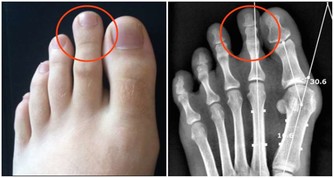

鞣質確實會與胃酸、果肉蛋白髮生作用,形成膠凍樣的物質。在胃消化食物不那麼順利的情況下,是導致胃結石的導火索。這個病不但治療麻煩、而且會導致胃潰瘍甚至是大出血。

但是這種情況並非常態,胃排空比較慢的人或者是在空腹吃了大量柿子、山楂和棗這類富含鞣質的水果時險情就出現了。